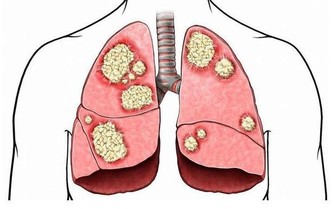

肝硬化發展到一定程度時易出現肝腹水,也就是腹中有太多積水,從而造成腹脹,導致放屁增多,以至於一天的排便次數大於10次。放屁次數跟肝硬化嚴重程度成正比,肝硬化病情越嚴重,放屁次數就越多。患有慢性肝炎、脂肪肝或酒精肝、長期服用藥物者,若放屁突然增多,還需及早去醫院做肝臟相關檢查,排除肝硬化的可能。

超重或肥胖者體內堆積太多脂肪,脂肪在肝臟中完成代謝,超出肝臟所承受的範圍,剩下的脂肪勢必會在肝細胞周圍堆積,從而導致肝細胞不能從血液中攝取營養,這裡面的代謝廢物也排不出體外,從而誘發脂肪肝。單純性脂肪肝並不可怕,適當地做好生活調理即可,但一直我行我素會逐漸發展成脂肪性肝炎,最終過渡到肝硬化或肝癌階段。因此應控制體重,從增加運動量和飲食方面入手,必要時還需借助醫學來減肥。